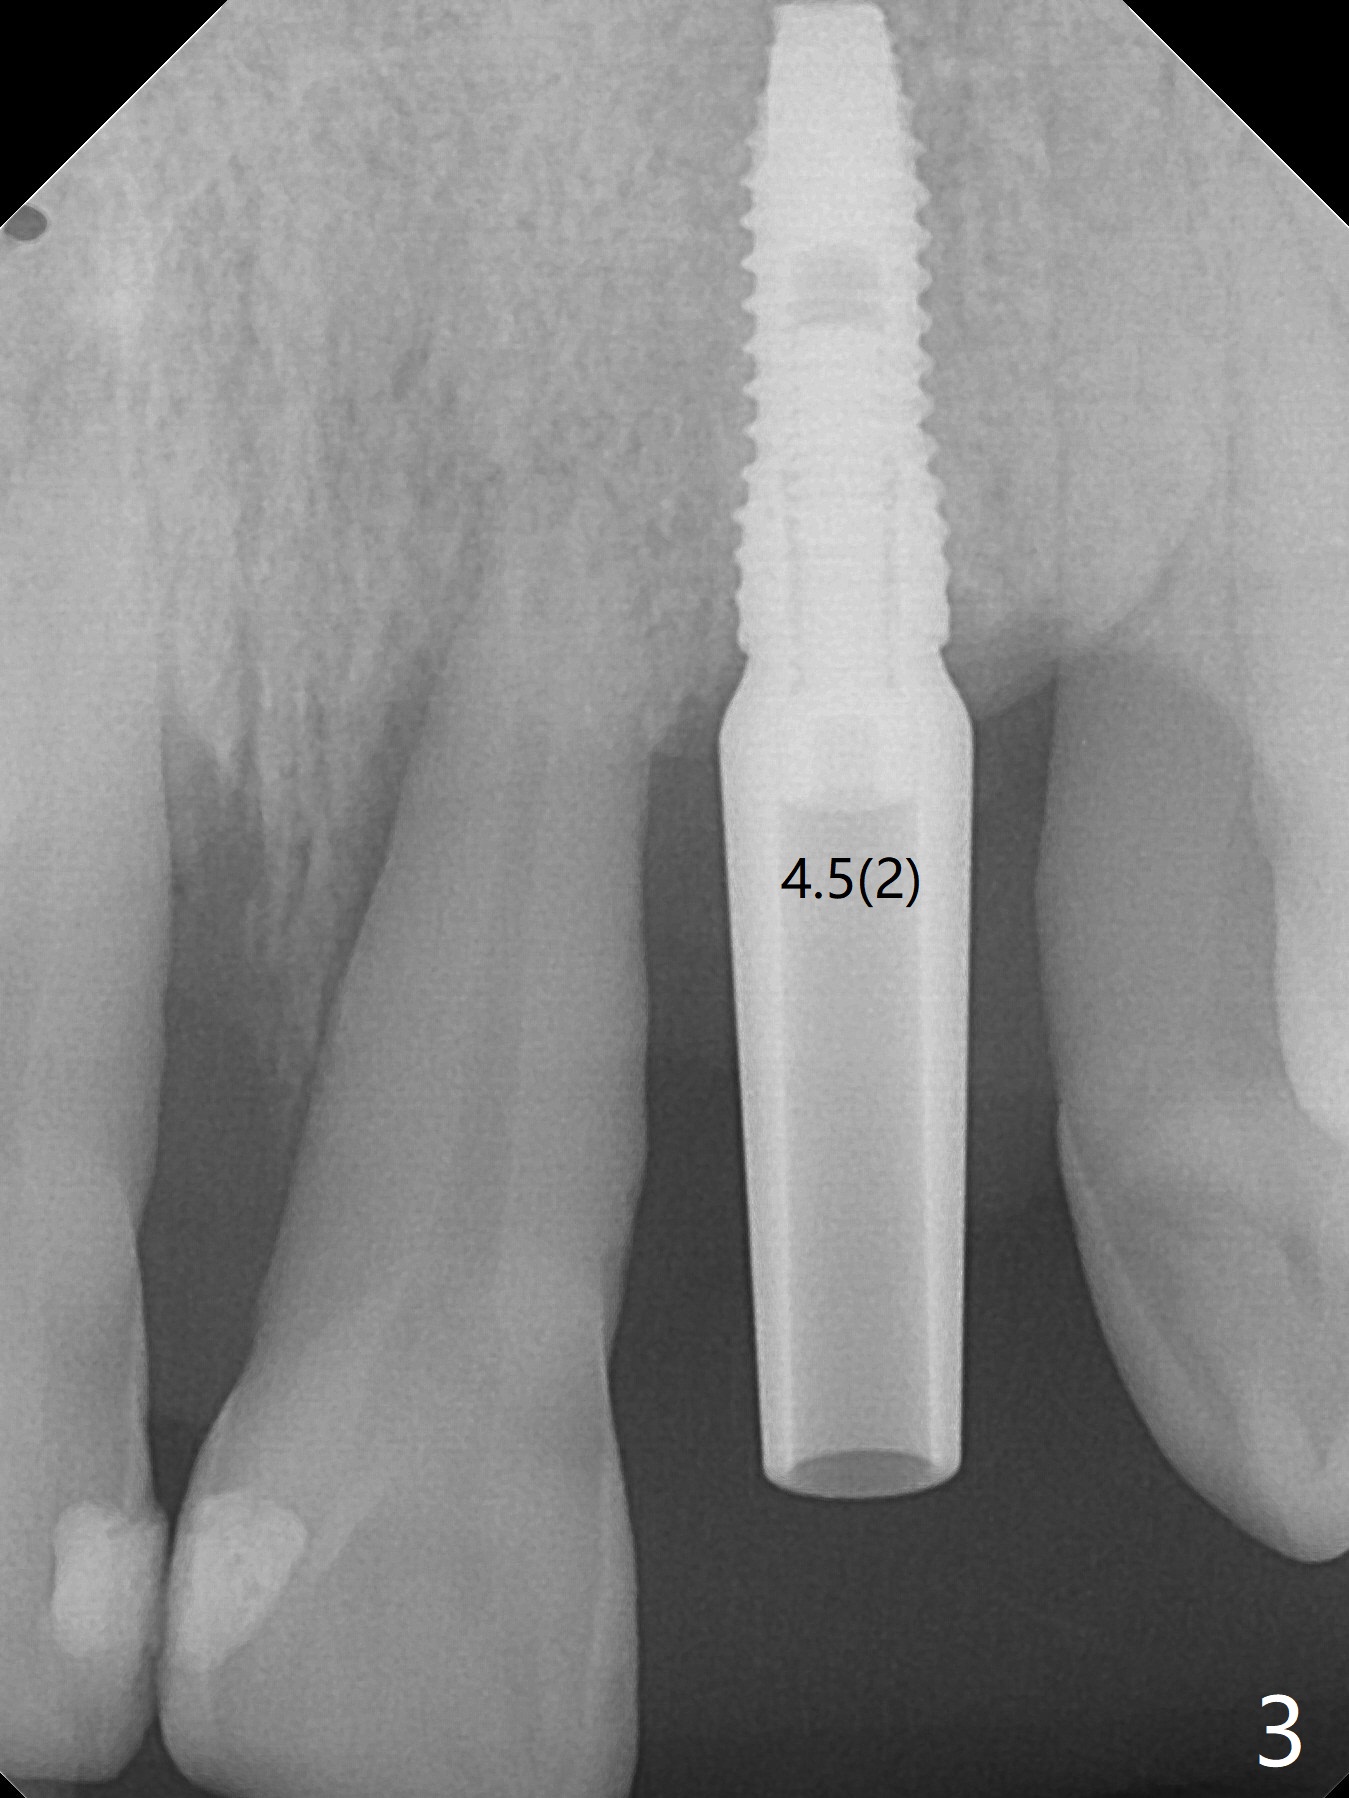

实验结果表明红管抽取上清液形成粘性骨块比白管快。左上二拔除,即刻徒手钻洞(图一),初步植入3.8x11.5毫米植体(图二),调整植体深度,然后放置直径4.5毫米长基台(图三,DIO UF; 牙龈厚度大于6毫米),最后填入大量粘性骨粉(图四,五 *),植体颊侧近中骨粉不足(图五 ^),之后再次充填骨粉。制作即刻修复物,颊侧瘘道和牙槽窝开口放置PRF膜。术后三周临时牙冠松动,取出后者,颊侧空间有两个区域:牙龈和骨粉(图六:白,黑星号)。由于脑部手术,术后接近一年病人回来取模。由于基台长,临时牙冠还没有脱落(图八)。牙龈袖正常(图九:*)。术后一年骨粉仍在植体,基台交界处(图十)。